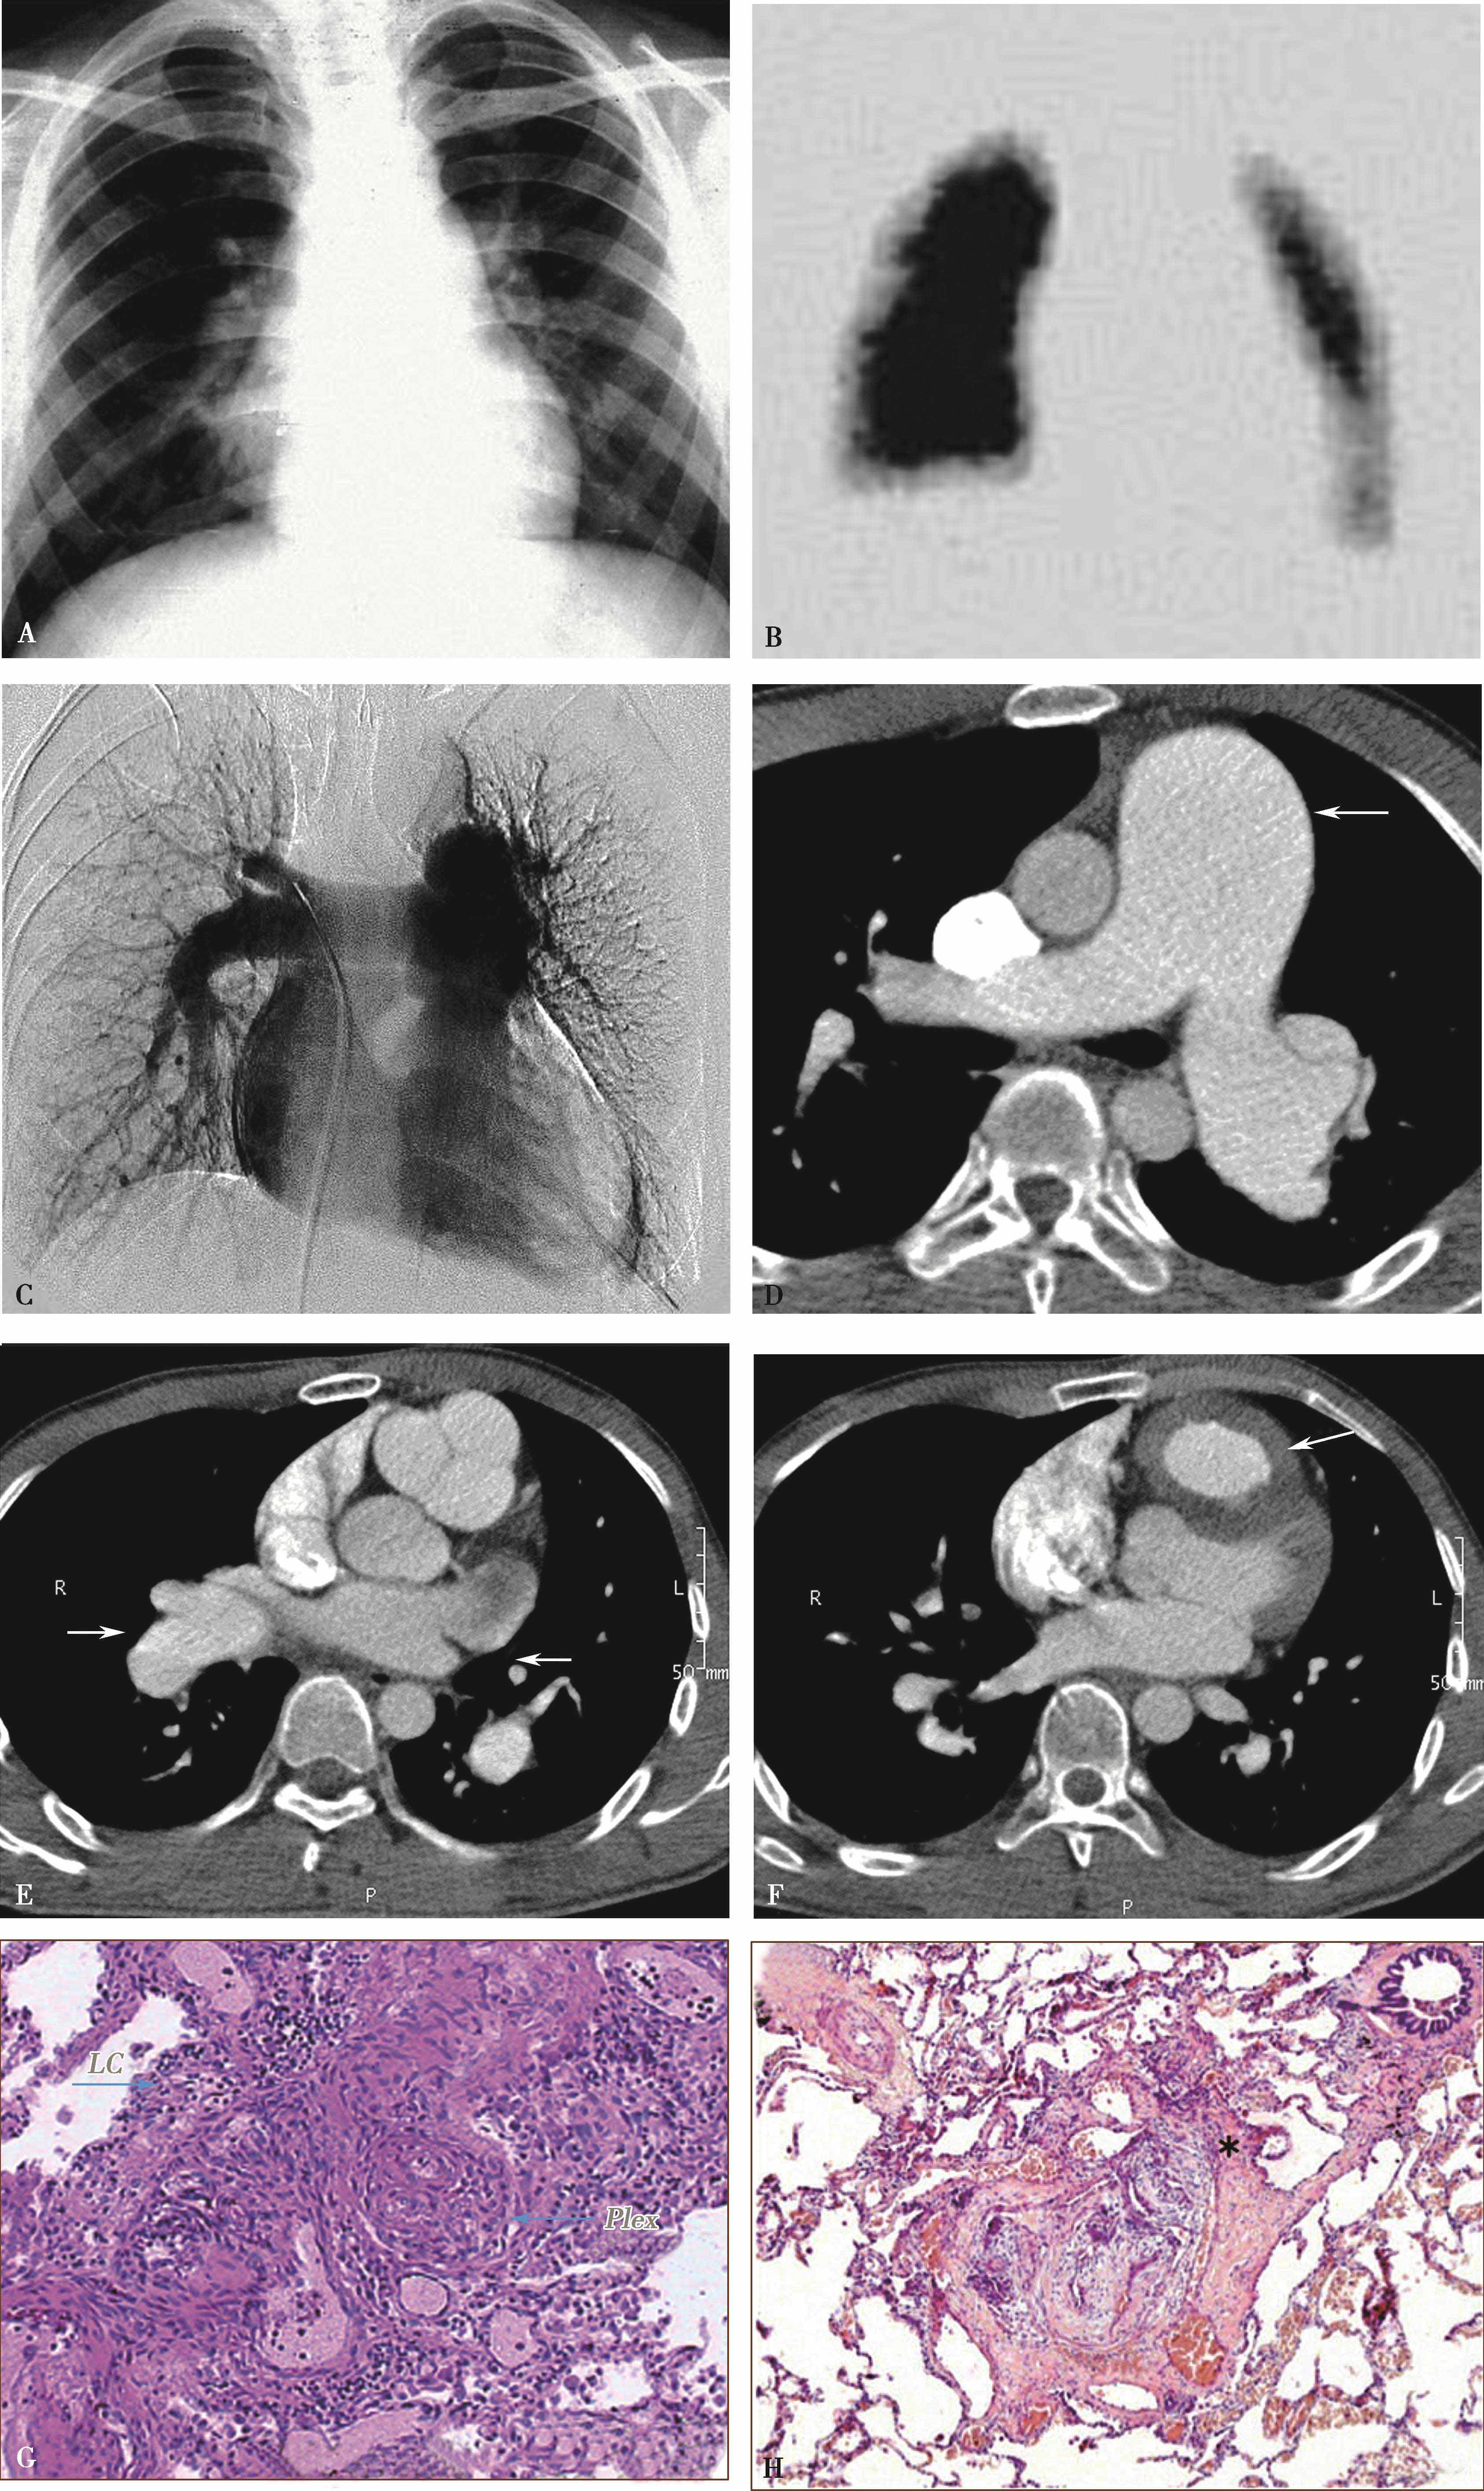

图8-7-1 女,21岁,反复咯血2年,胸闷气短1年半

CT横断扫描。A、B.多层重组;C、D.示主肺动脉及左右肺动脉内结节状充盈缺损,可见 “指压征”(↑),右肺动脉及左下肺动脉闭塞;前上纵隔中等密度影,考虑为纵隔转移(A▲)。肺动脉造影(E)示主肺动脉不规则充盈缺损,右肺动脉及左下肺动脉闭塞,术后病理诊断:低分化平滑肌肉瘤(F)

图8-7-2 男,44岁,因劳力性胸闷、气短2年余,加重1个月并出现双下肢水肿急诊入院

CT横断扫描ABCD示主肺动脉、右肺动脉干内巨大充盈缺损,膨胀性生长,累及右心室流出道(↑),主肺动脉明显扩张。肺动脉造影E,示主肺、左右肺动脉干及右下肺动脉管腔内充盈缺损(↑),两肺、左肺舌叶及下叶各基底支仅见稀疏肺动脉分支显影。病理诊断为恶性间叶细胞瘤。

图8-7-3 女,53岁,劳力性呼吸困难2个月余,偶尔咯血

A.CT横断图像,示主肺动脉及右肺动脉内充盈缺损-闭塞(↑);B.磁共振TIWI显示主肺动脉及右肺动脉中等信号(↑);C.磁共振增强扫描。管腔内充盈缺损,充盈缺损信号不均匀增强(↑);D. 18 F-FDG PET检查示该病灶呈放射性浓集(↑);E.手术切除大体标本,白色为瘤体;F.病理证实为原发肺动脉肉瘤。PA:主肺动脉;LPA:左肺动脉;RPA:右肺动脉

1.直接征象(图8-7-1~图8-7-3)

(1)主肺动脉或单侧肺动脉干管腔充盈缺损,大块状充盈缺损呈分叶、结节样(指压征),可以延肺动脉血管长轴向远侧蔓延。

(2)晚期肿块沿肺动脉长轴管腔膨胀性生长,可以充满主肺动脉、左右肺动脉干及叶段分支管腔,血管闭塞。CTPA检查对比剂存在于节结间呈分隔状,有一定提示。

(3)肿瘤可以发生于或累及肺动脉瓣、右心室流出道。如果有蒂存在,肿瘤可以有一定活动度。

(4)肿瘤依恶性程度,生长发展较快,肺门血管影圆隆增大,呈 “三叶草”征。

(5)远处转移:最常见的为肺和肋骨。